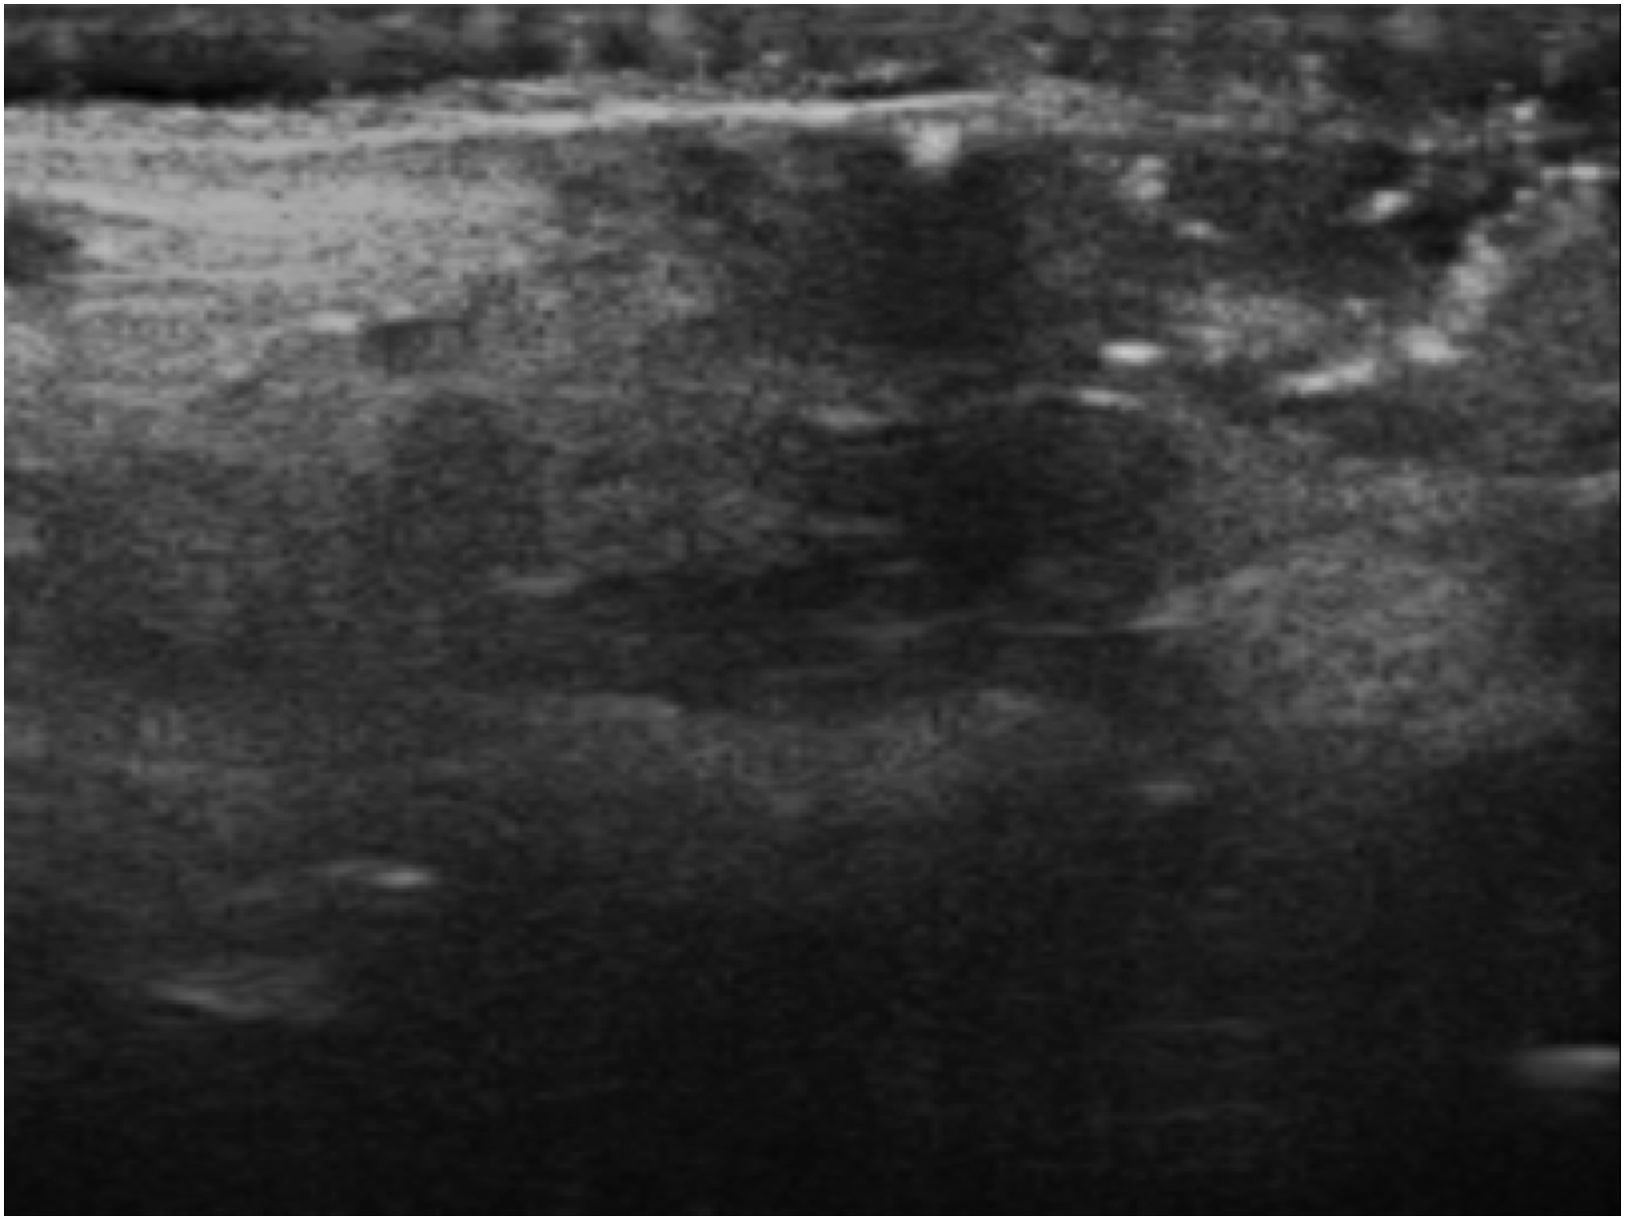

Other supplementary testsUltrasound examination was performed using an 18-MHz linear probe in B-mode, revealing a heterogeneous hypoechoic area with hyperechoic foci within it (Fig. 2).

An occupational history generally confirms the diagnosis.6 Certain tests such as biopsy or ultrasound may be useful; ultrasound shows hyperechoic foci corresponding to hair shafts.7 Among the differential diagnoses to consider are fungal or mycobacterial infection, Orf nodule, and other traumatic causes.6